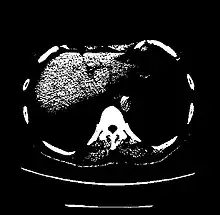

A practical application of this is in evaluation of tumors, where, for example, an adrenal tumor with a radiodensity of less than 10 HU is rather fatty in composition and almost certainly a benign adrenal adenoma.[30]

Values for different body tissues and material

| Parenchyma | Lung | −700 to −600[24] |

| Kidney | +20 to +45[7] | |

| Liver | 60 ± 6[25] | |